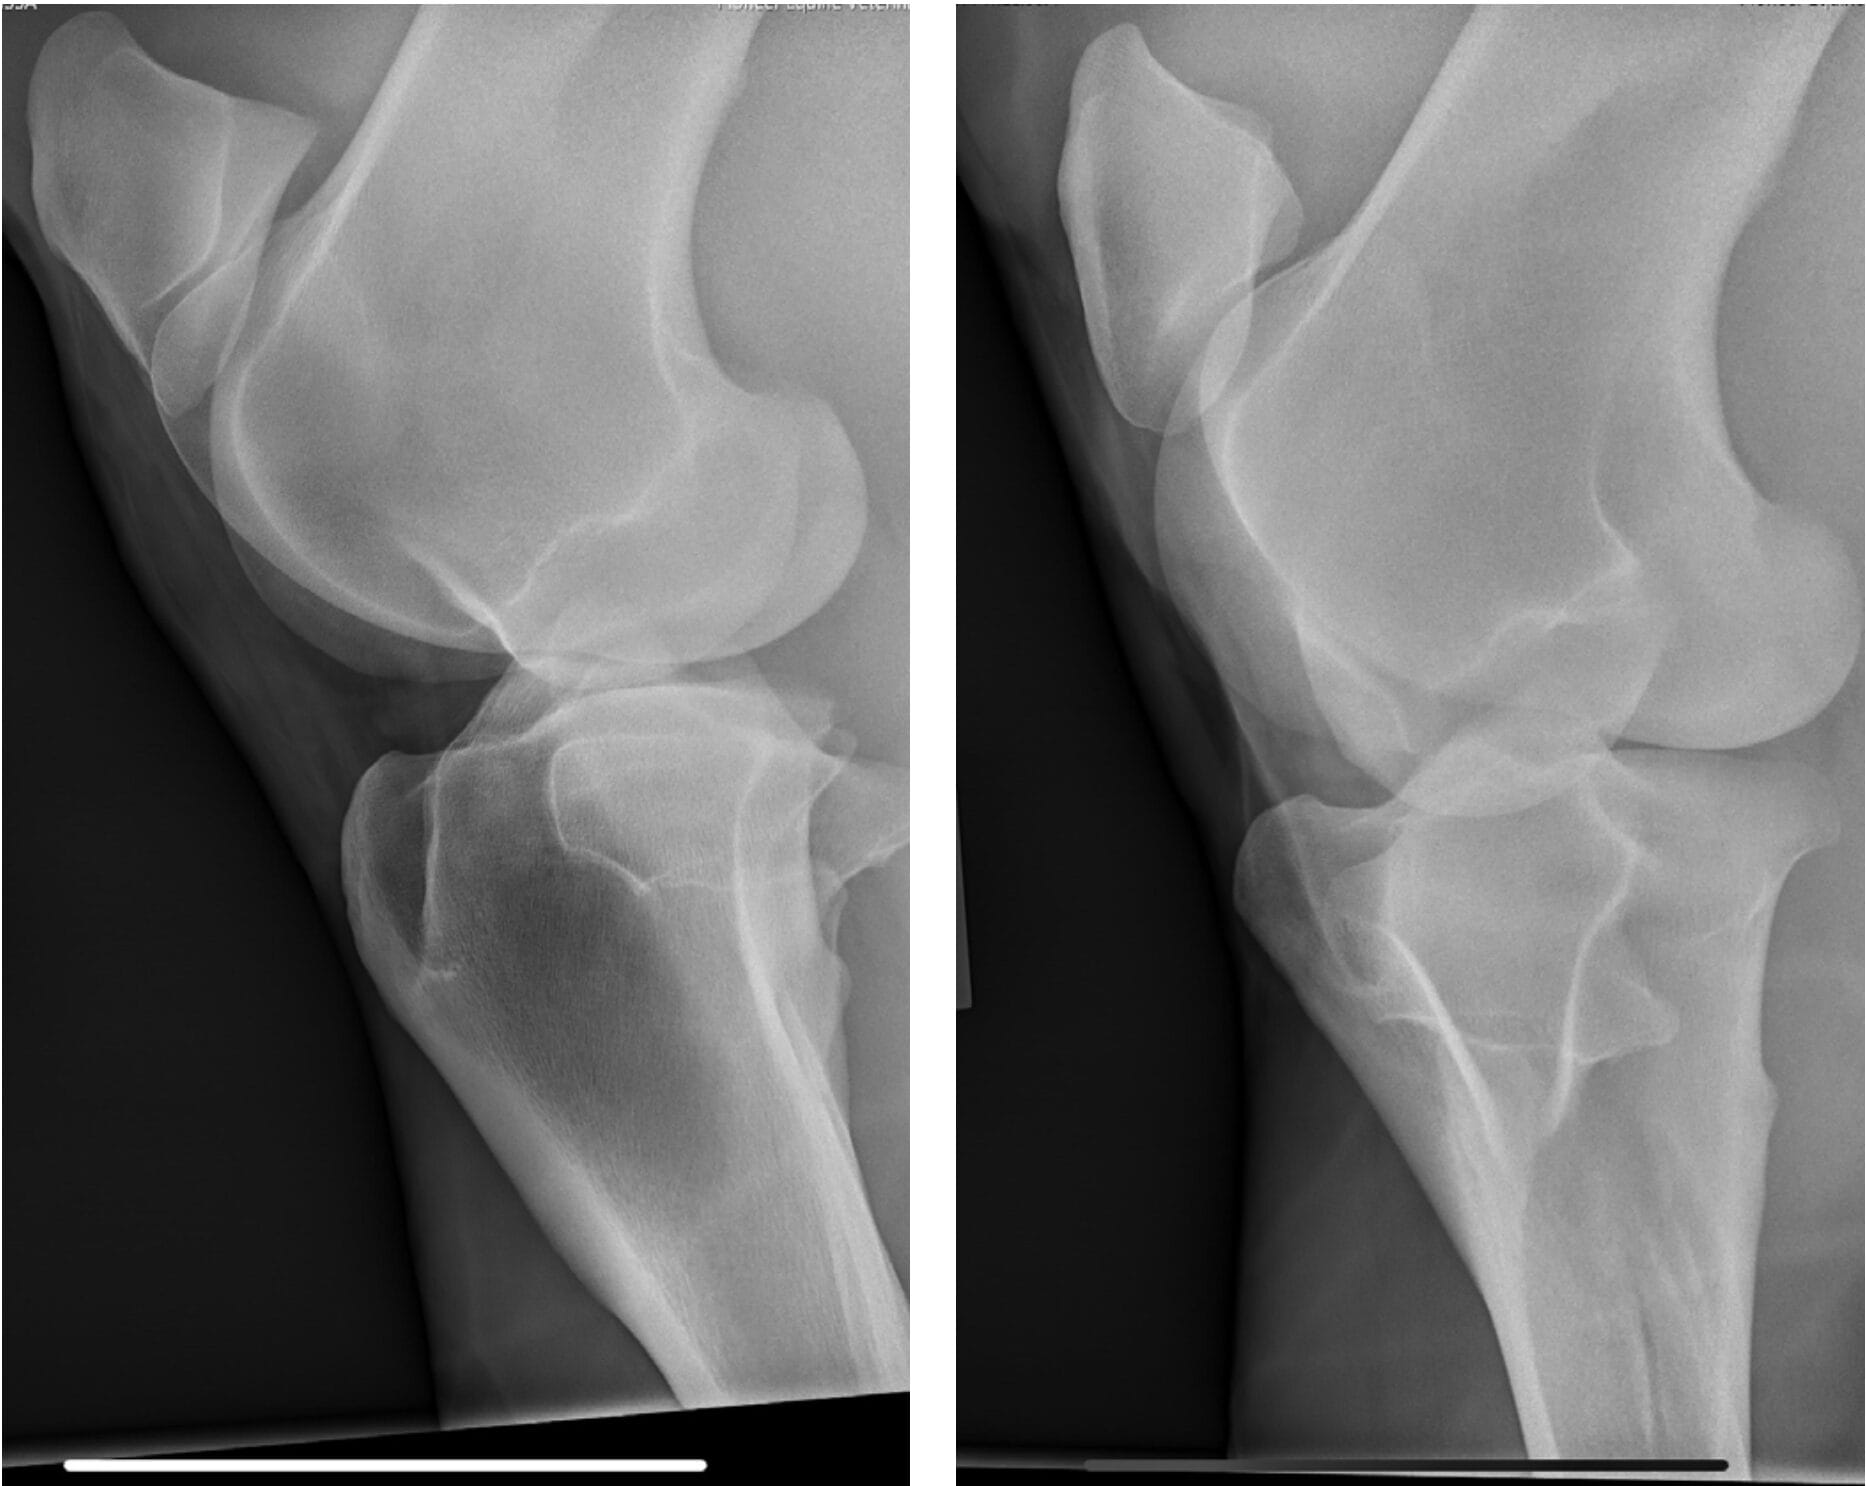

In April 2023, Bella developed a right hind lameness that was characterized by a toe drag, decreased push and mild abduction of the limb. The lameness was worse with the leg on the outside of the circle. She was negative to lower limb flexion and 1+ out of 5 positive to upper limb flexion. Lameness resolved with an intra-articular medial femorotibial block. Radiographs of the right stifle were unremarkable.